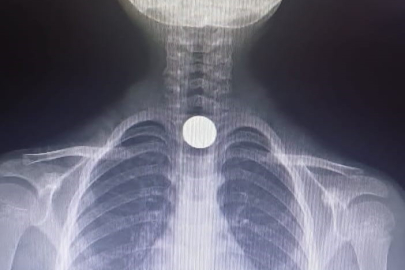

Olay, Mesudiye Mahallesi Sarmaşık Sokak'taki bir apartmanda meydana geldi. Evinde oynayan 5 yaşındaki Yusuf Z., halının üzerinde bulduğu 50 kuruşluk madeni parayı ağzına götürdü. Parayı yutan Yusuf, bir anda fenalaştı. Durumu fark eden aile, çocuğu otomobille İnegöl Devlet Hastanesi'ne götürdü. Hastanede doktorlar tarafından yapılan tetkiklerde paranın yemek borusuna takıldığı tespit edildi. Çocuk, boğazındaki paranın çıkarılması için Bursa Yüksek İhtisas Eğitim ve Araştırma Hastanesi'ne sevk edildi.